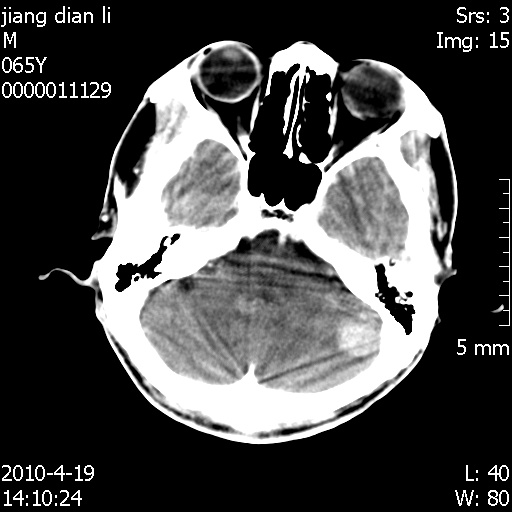

老年男性,突发左下肢无力1天,其余有价值的检查都没有。平扫ct值大约60hu,增强后ct值没什么改变,请大家讨论一下这个病例是什么?说明诊断理由。

左小脑、右大脑顶叶多发圆形高密度病灶,其周环状低密度影。考虑多发脑出血。隔期观察。